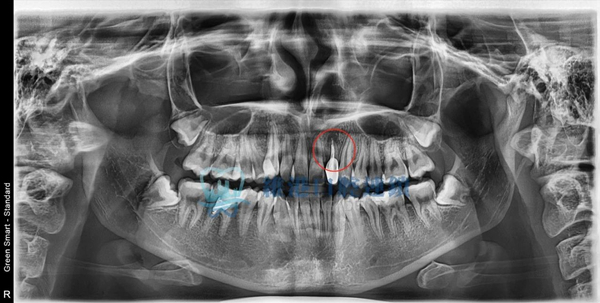

嚴重案例